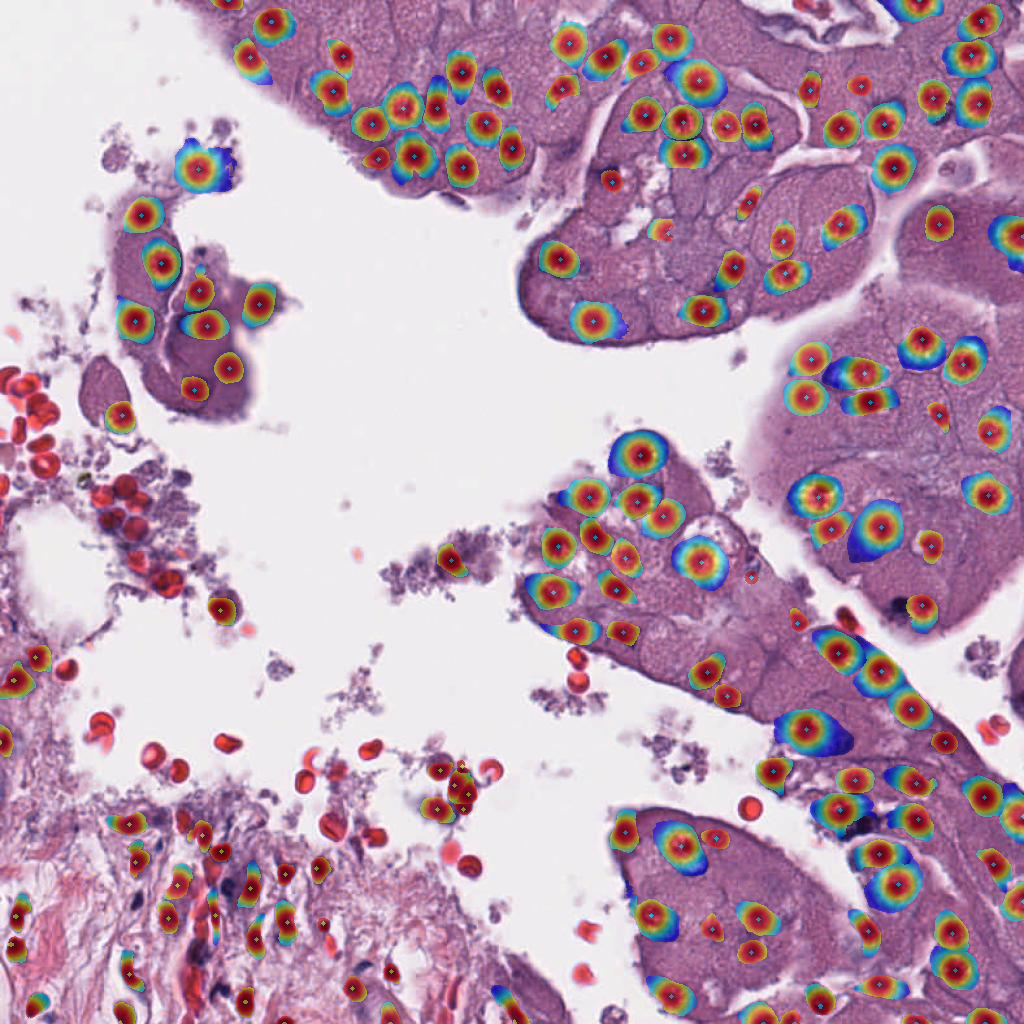

For the circle and soft IS ground truth formats we extract cell detection candidates from the segmentation prediction by applying skimage.feature.peak_local_max on the blurred foreground prediction (Figure 3), where:

and are the model predictions for the tumor cell class and background cell class respectively. Only cell candidates with a larger probability for the tumor or background cell class, compared to the background class, are considered. The cell candidate class is assigned as the foreground class with the highest probability. The hard IS requires a different approach, as cell instances are not trained to express a peak at the cell center and tend to overlap. For this reason, markers are extracted from the foreground prediction and then applied in a marker-controlled watershed segmentation to separate touching instance (more details in Appendix 0.B). The cell is assigned a class by majority vote of its pixel class predictions.